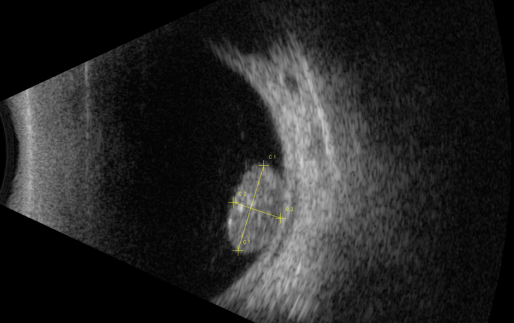

視網(wǎng)膜母細(xì)胞瘤的分類和治療

【文章導(dǎo)讀】視網(wǎng)膜母細(xì)胞瘤是嬰幼兒常見的眼內(nèi)惡性腫瘤,可危害患者的視力、眼球和生命。其惡性程度高,多發(fā)于兒童,尤其是3歲以下的兒童,常表現(xiàn)為白瞳癥,可侵及單眼或雙眼。 視網(wǎng)膜母

視網(wǎng)膜母細(xì)胞瘤是嬰幼兒常見的眼內(nèi)惡性腫瘤,可危害患者的視力、眼球和生命。其惡性程度高,多發(fā)于兒童,尤其是3歲以下的兒童,常表現(xiàn)為白瞳癥,可侵及單眼或雙眼。

視網(wǎng)膜母細(xì)胞瘤分類

視網(wǎng)膜母細(xì)胞瘤的分類

根據(jù)腫瘤的表現(xiàn)和發(fā)展過程可分為眼內(nèi)期、青光眼期、眼外期和全身轉(zhuǎn)移期。

1、眼內(nèi)期

開始在眼內(nèi)生長時(shí)外眼正常,因患兒年齡小,不能自述有無視力障礙,因此本病早期一般不易被家長發(fā)現(xiàn)。當(dāng)腫瘤增殖突入玻璃體或接近晶體時(shí),瞳孔區(qū)出現(xiàn)黃白色反光,如貓眼樣(“黑貓眼”),此時(shí)常因視力障礙而瞳孔散大、白瞳癥或斜視被家長發(fā)現(xiàn)。